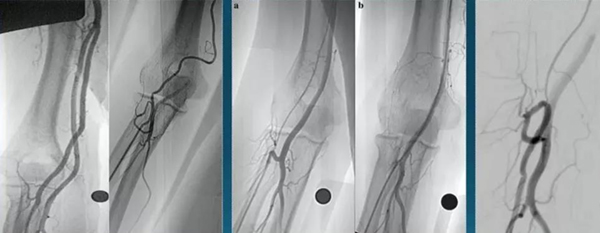

桡动脉存在不同的血管变异可能,上图所示为几种不同的变异,从左到右分别是5种变异的桡动脉,第1、2种变异情况仍可以完成经桡动脉入路血管造影,第3-5种可能因路径迂曲,血管管径纤细而不适合行介入手术。